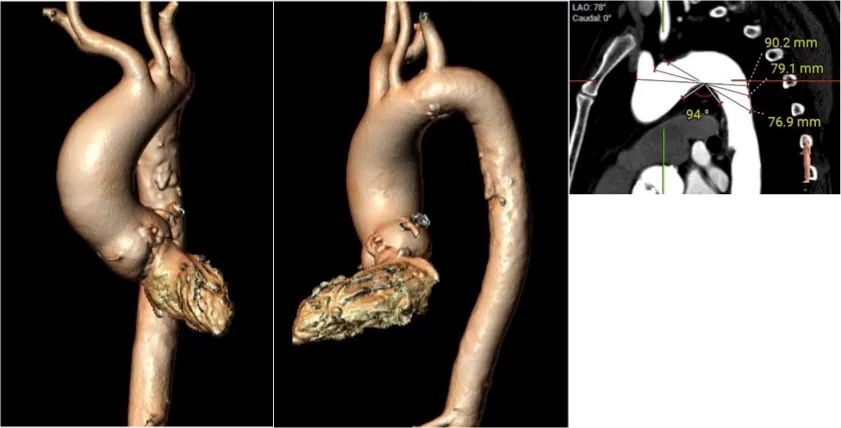

主动脉弓:

股动脉入路:

Type0型二叶瓣自身具有定位困难的挑战,植入策略的观点也各有不同,对瓣膜性能要求更高,既需要在二叶瓣特殊结构挤压下牢固锚定,又要贴合鱼嘴状结构最大限度避免瓣周漏的发生。同时此患者合并存在主动脉弓距小,弓角锐角的特点,对瓣膜系统的整体通过性能提出挑战。